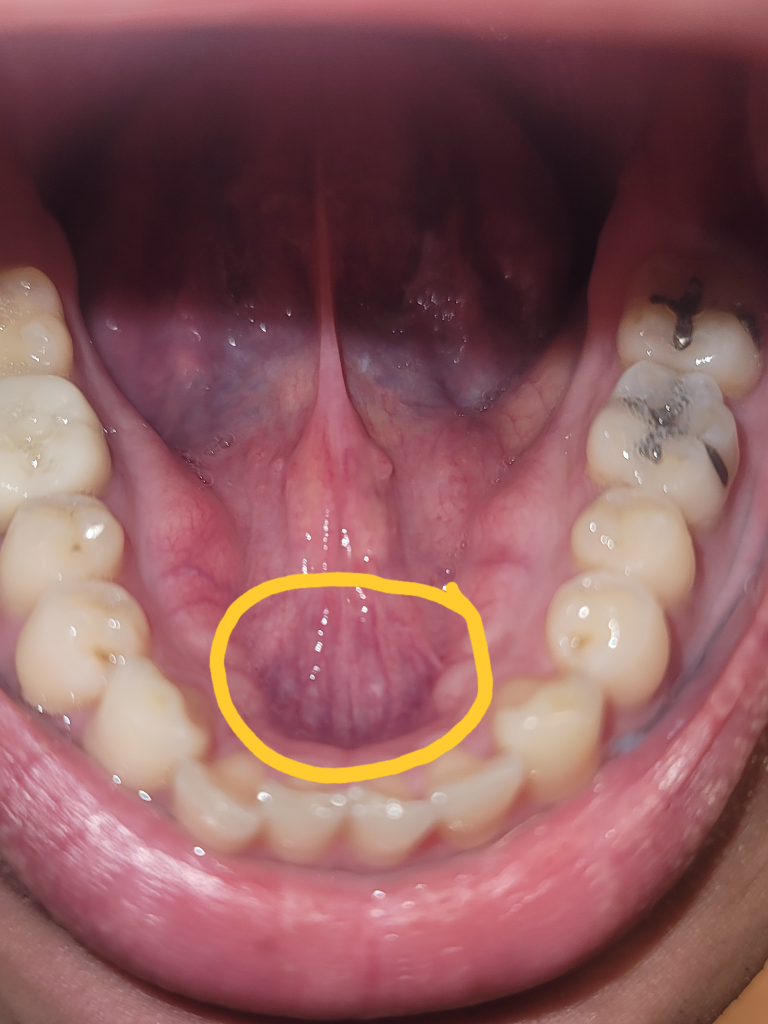

혀 아래 구강저 부분에 딱딱한 알갱이 같은 것들이 있습니다.

거울로 보면 눈으로 보이지는 않지만 혀나 손가락으로 만져는집니다.

왼쪽 3개, 오른쪽은 2개 정도가 있는 것 같고 하나당 3~4mm 정도 되는 동그란 구슬 모양입니다.

혀로 만지면 움직이는 것도 있고 움직이지 않는 것도 있습니다.

예전부터 있었던 것 같은데 기분탓인지는 몰라도 예전보다 커진 것 같습니다.

정상적인 구조물인지 병원에서 검사를 해야 하는지 궁금합니다...

사진상에 노란색 선 안 쪽에서 만져집니다.